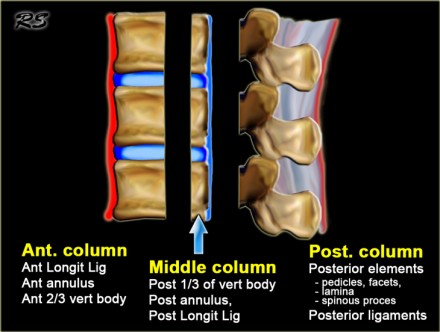

On the left the three column model of Denis.

This model is used to predict the soft tissue injury from bone injury.

Spinal stability is dependent on at least two intact columns.

When two of the three columns are disrupted, it will allow abnormal segmental motion, i.e. instability.

So a simple anterior wedge fracture or just sprain of the posterior ligaments is a stable injury.

However a wedge fracture with rupture of the interspinous ligaments is

unstable, because the anterior and the posterior column are disrupted.

A burst fracture is always unstable because at least the anterior and middle column are disrupted.

Criteria to predict soft-tissue injury from bony injury are:

- Angulation greater than 20 degrees.

- Translation of 3.5 mm or more.